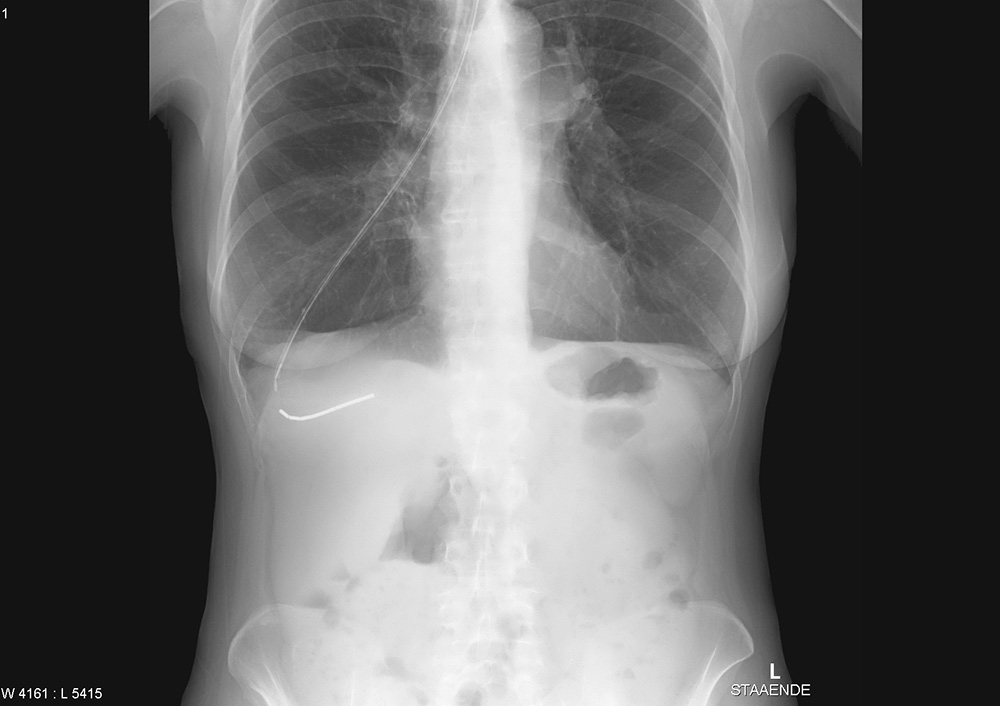

En kvinne i 60-årene var innlagt med svelgevansker og ernæringsproblemer. Hun var fra tidligere diagnostisert med supraglottisk plateepitelcancer og behandlet med utvidet strålefelt mot halsen og med cytostatika. Ved denne innleggelsen fikk hun lagt ned en tynn nasogastrisk sonde. Sonden hadde ytre diameter 1,95 mm og en stålmandreng. Den lot seg tilsynelatende føre ned ukomplisert. Ved instillasjon av 10 ml luft hørtes ikke bobler som normalt over magesekken. Røntgen av nedre thorax og øvre abdomen viste at sonden hadde fulgt bronkialtreet langt ut i høyre lunge (bilde til venstre). Sonden ble fjernet, men kort tid etter fikk kvinnen store pusteproblemer og stansalarmen måtte aktiveres. Røntgen thorax viste en stor høyresidig pneumothorax (bilde til høyre). Den ble vellykket behandlet med kirurgisk anlagt pleuradren.

Pasienter med gjennomgått cancer og strålebehandling i øre-nese-hals-området har ofte store ernærings- og svelgevansker som gjør det nødvendig å legge ned en nasogastrisk sonde. Samtidig er ofte anatomiske forhold endret og vanlige reflekser svekket, slik at man må være ekstra varsom ved nedlegging av sonden. Det finnes imidlertid også flere beskrivelser av pasienter uten strålebehandlet kreftsykdom, noen med trakeostomitube og orale tuber med oppblåst mansjett, som har fått lagt ned tynn ernæringssonde ut gjennom pleura uten symptomer (1), for så å få en alvorlig pneumothorax i det ernæringssonden dras tilbake. Dette skjedde også hos vår pasient. Pleuradrenberedskap anbefales derfor før ernæringssonden trekkes ut (1).